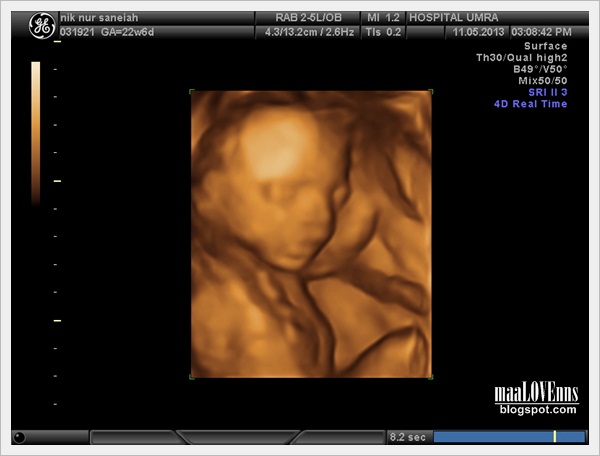

Date : 11th May 2013

Time : 1pm - 3pm

Venue: Poliklinik Umra

First thing first...its a boy!!!!

Alaaahh...sekarang ni teknologi dah canggih manggih..dah macam2 "d" dah scan boleh buat. Mama buat utk iman nur zahra dulu tahun 2011 pon dah 3D and 4D scan. Masa scan tu memang dah boleh confirm dah boy ke girl. Takde nak risau kot2 scan lain, keluar lain ke ape kan!

Dengan ini, kami dengan bangganya mengumumkan bahawa kami bakal menamakan boboy kami ni dengan nama....

Iman Zariff Bin Mohamad Akmal Azim!!!

Jom kite tengok gambar-gambar lain yang doc capture masa detail scan tu ye..

Seperti biasa...awal2 baby memang nampak sangat kurus dan takde isi. Masa ni baru masuk 24minggu. Macam kakak zara dulu jugak. Mula2 scan tu muka kurus je, masa tu mama dan papa memang sangat risau takot baby tak ckup zat ke ape, tp memang mengikut perkembangan pon macam tu. Lepas beberapa bulan kemudian baru masuk isi..baby jadi tembam..bam..bam..

Oke...jom kite zoom in tang muka pulak ye. Tengok agak-agak ikot muka sapa. Kalau dulu..si cik mek iman nur zahra tu memang sah2 la muka mama. Keluar sebijik sejibon muka mama.

Tapi iman zariff ni mama tak sure pulak. Ramai member mama ngan papa cakap muka iman zariff ni bakal jadi macam sebijik sejibon muka papa!! hahaha..we will see soon!!